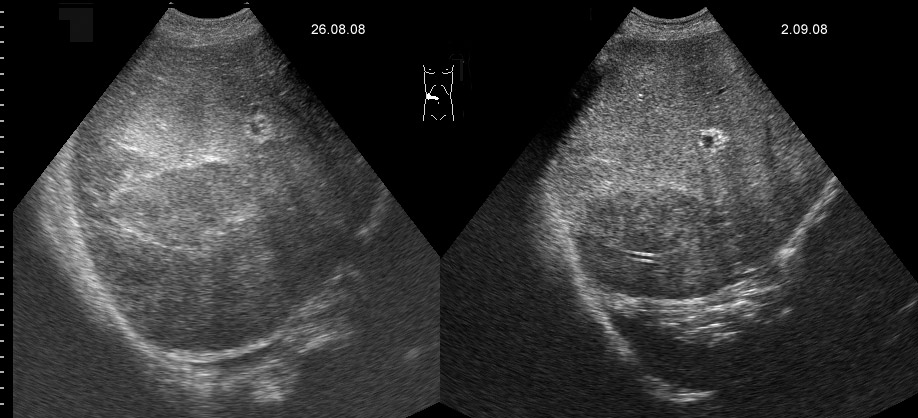

Маленький абсцесс печени до и на фоне 1 недели АБ-терапии

Те, которые не можем задренировать - проводим АБ-терапию.

abscess-one_week_treatment.jpg

А какие ограничения для дренирования были в данном случае?

Плохая доступность. Был расположен очень высоко и был небольших размеров.

Решено было вести консервативно.